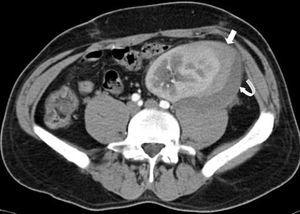

An emergency Doppler echocardiogram was performed showing the graft of 121 mm in the left iliac fossa (LIF) with increased cortical echogenicity, good perfusion, RF: 1. An organized perirenal haematoma of 93 x 37 x 60 mm was identified. To complete the study, a CT scan with contrast was performed showing enhancement of all the kidney with 2 hypoechoic linear lesions. These were interpreted as a fracture of the anterior pole of the graft (Figures 1 and 2). No aneurysm or kidney tumours were observed. In view of the patient being haemodynamically stable and the diagnosis of advanced kidney rupture, emergency surgery was ruled out. An initial session of haemodialysis was performed; diuresis began again after 48 h with progressive improvements in the analytical parameters. The diagnosis of AR was ruled out given the patient’s good progress without having taken other therapeutic measures and the fact that his immunosuppressor levels were within the normal range.

Figure 1. CT scan of the graft showing a perirenal collection of the graft compatible with fracture of the inferior pole (thin arrow)